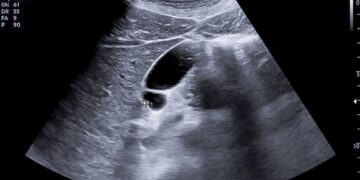

Bario sulfatas dažniausiai suleidžiamas klizmos būdu į tiesiąją žarną. Gydytojas ar slaugytojas paaiškins, kaip reikėtų pasiruošti šiam tyrimui. Jei instrukcijų negavote ar jos neaiškios, prieš procedūrą pasitarkite su gydytoju.